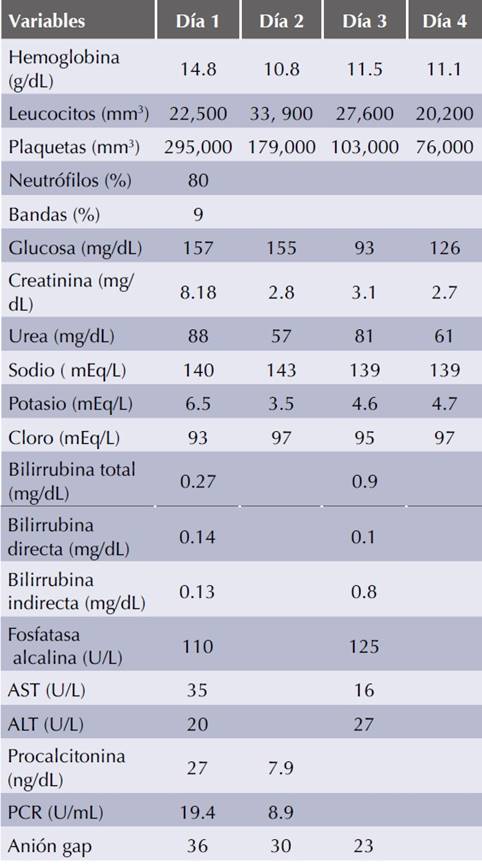

Paciente femenina de 72 de edad con antecedentes heredofamiliares de diabetes mellitus 2. Diagnóstico de diabetes mellitus 2 de 17 años de evolución con tratamiento regular con metformina 850 mg cada 12 horas, glibenclamida 5 mg cada 12 horas y con aparentemente buen control metabólico. Ingresó al servicio de Urgencias por dolor abdominal tipo cólico, evacuaciones diarreicas sin moco ni sangre, fiebre no cuantificada, ataque al estado general y somnolencia de tres días de evolución. A la exploración física se encontró confusa y somnolienta, con signos clínicos de deshidratación, taquicárdica, taquipneica, con hipotensión arterial y oliguria. El abdomen se encontraba globoso, con peristalsis presente, doloroso a la palpación en forma generalizada y sin datos de irritación peritoneal. En los exámenes de laboratorio de ingreso se documentó leucocitosis con neutrofilia y ban-demia, además de cifras elevadas de creatinina sérica y urea, hipercalemia, acidosis metabólica de anión gap elevado e hiperlactatemia (Cuadro 1). El abordaje diagnóstico se complementó con una tomografía axial de abdomen, en la que no se evidenció una causa orgánica del dolor abdominal y tampoco se observaron datos de isquemia intestinal (Figura 1). Se integraron los diagnósticos de sepsis grave con foco infeccioso gastrointestinal, daño renal agudo AKIN 3 secundario a necrosis tubular aguda con criterios dialíticos de urgencia, además de acidosis láctica grave secundaria a choque séptico y metformina. A su ingreso la paciente tuvo insuficiencia respiratoria que requirió ventilación mecánica y recibió tratamiento temprano basado en metas para pacientes con sepsis y choque séptico con soluciones cristaloides intravenosas, antibiótico intravenoso con piperacilina/tazobactam ajustados a la función renal, bicarbonato intravenoso, infusión de norepinefrina a dosis elevadas y tratamiento hemodialítico con sesiones de hemodiálisis intermitentes prolongadas. La evolución clínica durante las primeras 48 horas de tratamiento fue satisfactoria; con mejoría del estado ácido-base y de la cifra de presión arterial media que permitió la disminución progresiva hasta dosis mínimas del vasopresor, así como disminución en los marcadores inflamatorios procalcitonina y proteína C reactiva. Sin embargo, posterior a 48 horas de tratamiento la paciente persistió con concentraciones elevadas de lactato en sangre a pesar de tres sesiones de hemodiálisis, cifras de presión arterial media por arriba de 65 mmHg con dosis mínima de vasopresor y pruebas de funcionamiento hepático dentro de límites normales (Figura 2). Se agregó dobutamina al tratamiento y como parte del reabordaje diagnóstico de la hiperlactate-mia persistente se realizó una TAC de tórax y abdomen que documentó múltiples y extensos infartos hepáticos secundarios a trombosis de la arteria hepática (Figura 3). La paciente tuvo disfunción orgánica múltiple resistente a tratamiento médico y finalmente falleció al cuarto día de hospitalización.

AST: aspartatoaminotransferasa; ALT: alaninoaminotransfe-rasa; PCR: proteína C reactiva.

Cuadro 1 Evolución de los parámetros de laboratorio